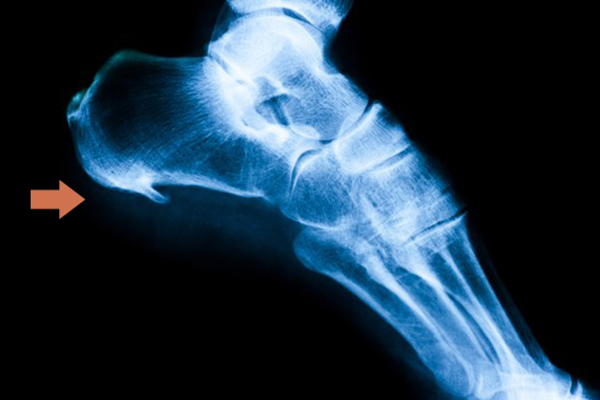

In questo articolo ti forniamo tutte le informazioni che devi sapere sullo sperone calcaneare, una calcificazione nel tallone che si sviluppa a seguito di una